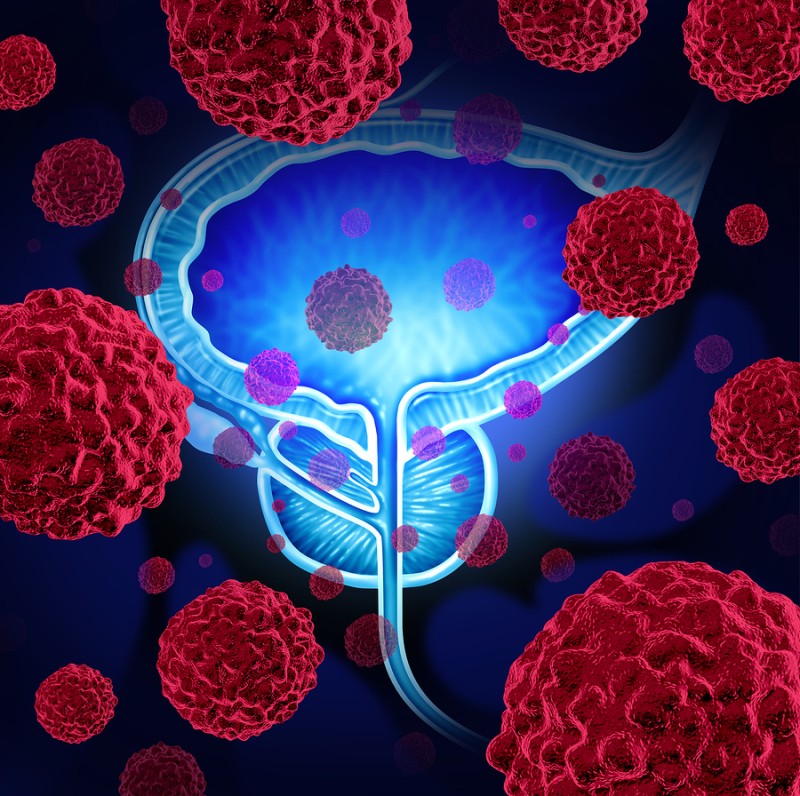

photos of prostate cancer

Prostate Cancer Illustration Stock Illustration – Illustration of …